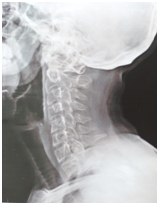

The baseline score (before starting our treatment) on BASDAI was ‘4.5’ and after 6 months completion of treatment the score on BASDAI was reduced to ‘0.9’ i.e., there was ‘80%’ of improvement found. Good improvement was found in ‘fatigue/tiredness’ (80% relief), ‘neck/back/hip pain’ (75% relief), ‘tenderness’ (80% relief), and ‘intensity as well as duration of morning stiffness’ (88% relief). Patient’s sleep, appetite and quality of life were improved. There was noticeable improvement observed (thorasic kyphosis/stooping of neck forward) in X– Ray of cervical spine (Figures 3&4). Knee joint pains were totally relieved and patient’s posture got improved along with relief in low back ache and neck pain. No adverse effects were reported by the patient. The patient got clinically meaningful improvement by internal medicines along with dietary restrictions (advised to avoid dairy products and to drink hot water) and life style changes. Ayurvedic treatment seems to be promising in the management of AS with in short period of time and without causing any adverse effects.

Figure 3 X – Ray of Cervical spine – Lateral view (dated on 08.08.2016).

Figure 4 X – Ray of Cervical spine – Lateral view (dated on 20.12.2016).